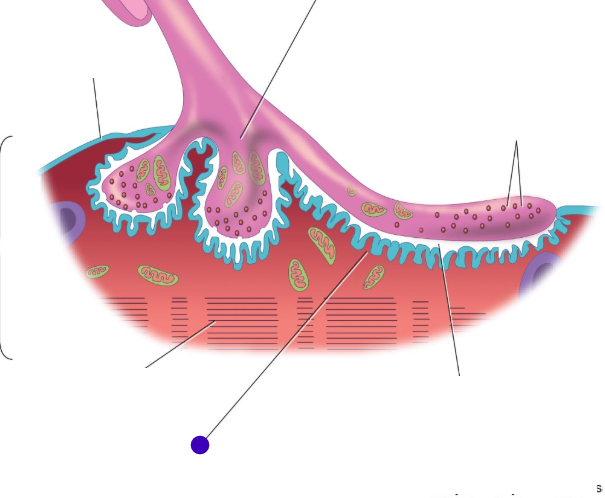

Motor end plate

knowt flashcard image